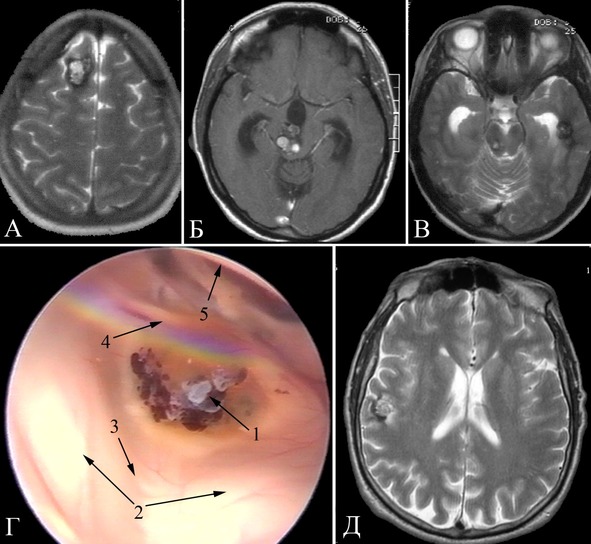

Клиническое наблюдение №5.

Больной Б, 43 года.

Из анамнеза известно, что эпилептические приступы беспокоят в течение 20 лет. С течением времени отмечалось учащение и нарастание тяжести приступов. К моменту госпитализации приступы беспокоили до нескольких раз в неделю. Характер приступов: 1) ауры продолжительностью 2—3 секунды в виде «наплыва» мыслей и воспоминаний, состояние по типу дереализации затем аутомоторный пароксизм с амнезией события, 2) те же приступы с последующим переходом в генерализованный клонико-тонический припадок. Продолжительность приступа неизвестна, так как пароксизмы амнезирует. Принимал различные антиконвульсанты в дозах не менее средней терапевтической с недостаточным эффектом. При МРТ выявлена кавернома правой височной доли (рисунок 30).

Рисунок 30. Клиническое наблюдение №5, МРТ больного в аксиальной проекции. А – режим Т2. Б – режим Т1.

Выполнено удаление каверномы правой височной доли в сочетании с передней лобэктомией и амигдалогиппокампэктомией (рисунок 32).

В послеоперационном периоде отмечено появление левосторонней верхнеквадрантной гомонимной гемианопсии, больной выписан на 8-й день, рекомендован постоянный прием антиконвульсантов.

Больной в течение двух лет находится на амбулаторном наблюдении. Беспокоят редкие сложные парциальные приступы. Продолжает принимать антиконвульсанты. При контрольной МРТ подтверждено полное удаление каверномы (рисунок 33). При повторных ЭЭГ данных за эпилептиформную активность не получено.

Рисунок 32. Клиническое наблюдение №5. Интраоперационные фотографии больного Б. Лобно-височная трепанация справа, резецированы передние отделы правой височной доли (1). А – удаление каверномы (2). Б – доступ в полость височного рога бокового желудочка, цифрами отмечены передние отделы гиппокампа (3), хориоидальная щель (4). В – Укладка электрокортикографического электрода (5) вдоль гиппокампа. Г – субпиальная резекция гиппокампа, 6 – твердая мозговая оболочка дна средней черепной ямки.

Рисунок 33. Клиническое наблюдение №5, контрольные МРТ больного Б. в аксиальной проекции. А – режим Т2. Б – режим Т1.

Данный клинический пример демонстрирует эффективность методики амигдалогиппокампэктомии у больного с длительным анамнезом эпилептических припадков, обусловленных наличием каверномы неокортикальной височной локализации.